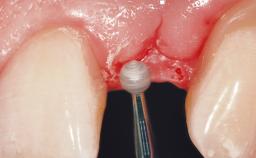

Late Flapless Placement of an Implant in a Maxillary Left Central Incisor Site

Soft Tissue Grafting Simultaneous

Soft Tissue Anatomy Intact Defective

Soft Tissue Contour and Volume Slightly compromised